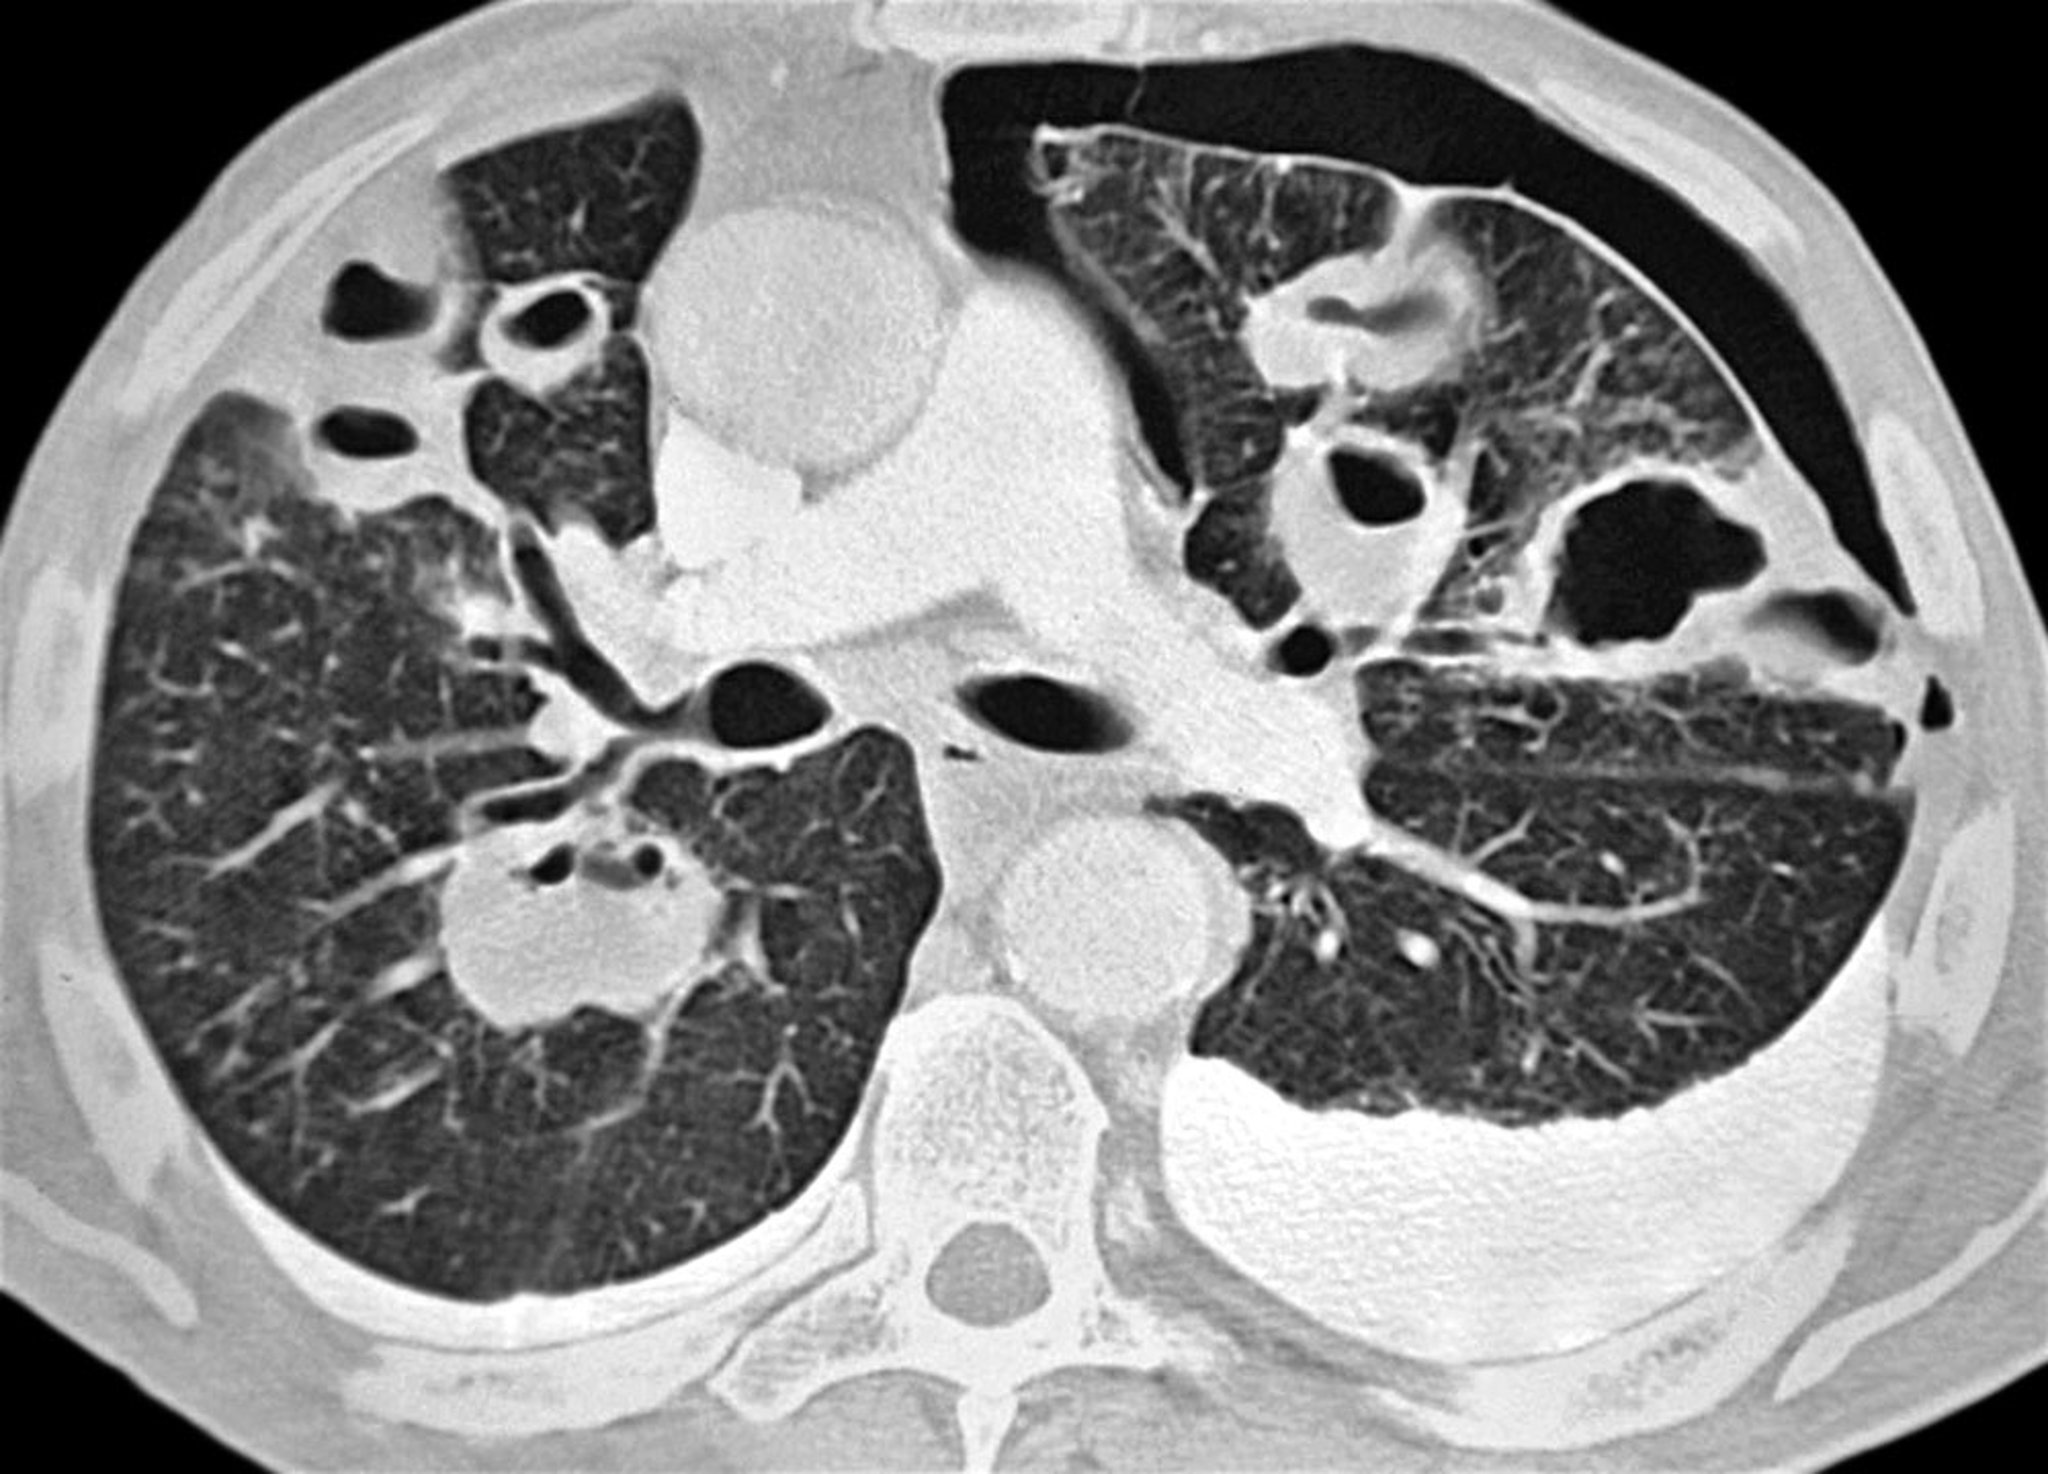

Pneumothorax (CT Scan)

This axial CT scan shows a left-sided pneumothorax in a patient with bacterial pneumonia. Multiple abscesses and bilateral pleural effusions (more prominent on the left) are seen as well.

PNMB/SCIENCE PHOTO LIBRARY